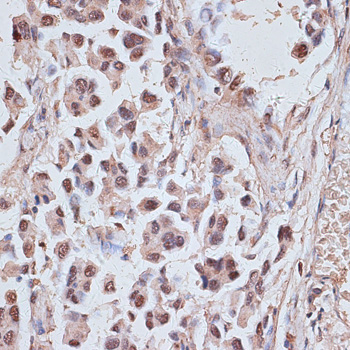

Immunohistochemistry of paraffin-embedded human lung cancer using NR5A2 antibody. |